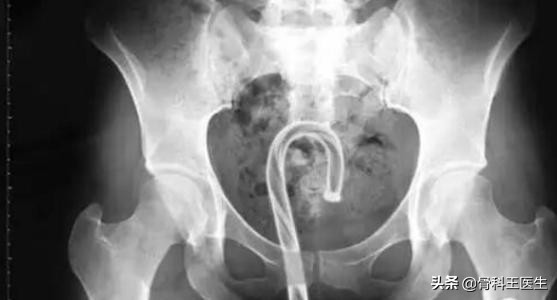

下图你们知道是什么吗?王医生羞羞的表示并不认识:

不认识就不发了,我们发一些认识的:

5、阴道、尿道取异物:

负责任的讲,肛门能进去的阴道都能塞进去:

我只发两张图,笑笑不说话:

尿道呢?尿道其实塞的东西也不少!